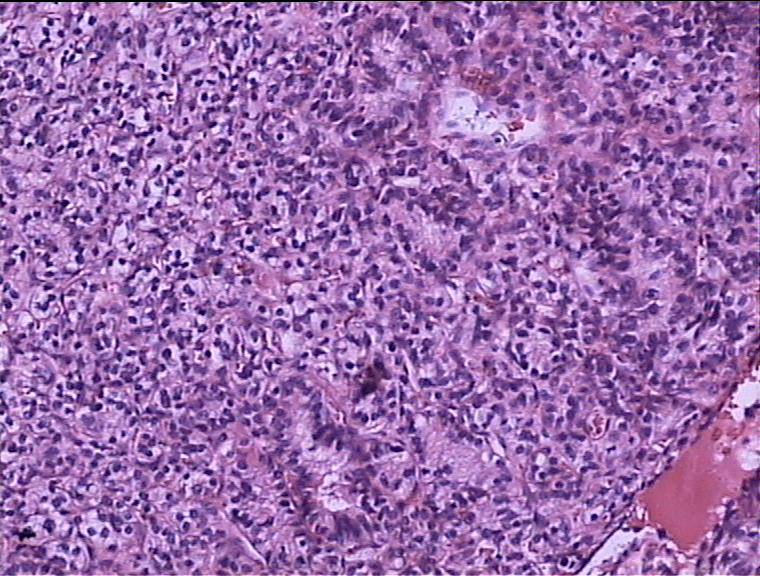

病理结果,腺泡样软组织肉瘤!

腺泡样软组织肉瘤

极为罕见,其组织来源不明。

起源于肢体软组织者称腺泡状软组织肉瘤,原发于骨内者,称骨腺泡状肉瘤。

本病大多发生于股部、臀部及小腿深侧肌群,上肢和其他部位少见。